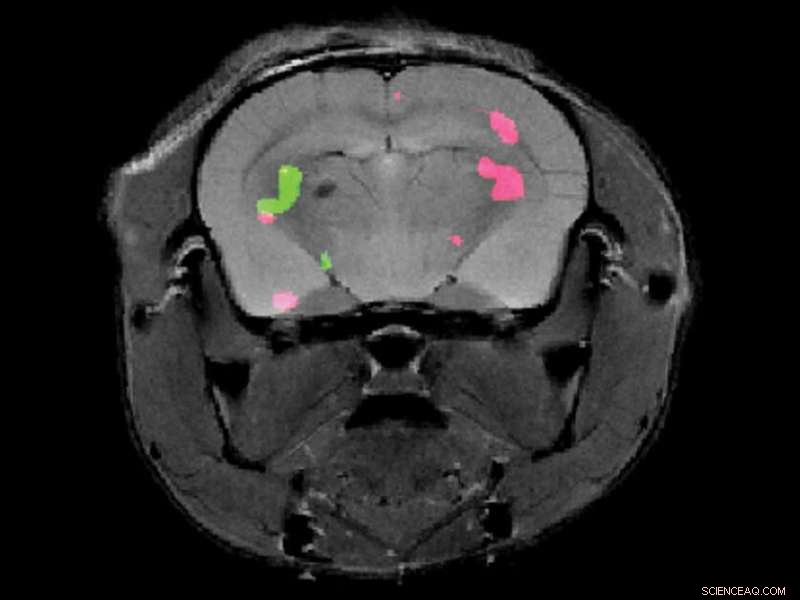

Two different proteins expressed in a mouse brain are revealed by dual-color MRI. Credit: Weizmann Institute of Science

Dr. Hyla Allouche-Arnon, a staff scientist in Bar-Shir's lab, led the study, in which Bar-Shir's team and other researchers collaborated with Prof. Sarel Fleishman and Dr. Olga Khersonsky of the Biomolecular Sciences Department. Applying the method in live mice, the scientists used exceptionally powerful MRI equipment with a magnet of about 15 tesla—one of only a handful of such machines in the world. The scans picked up the frequencies of the molecular probes, revealing the exact positions of the cells that expressed each of the proteins and marking them in green and pink.